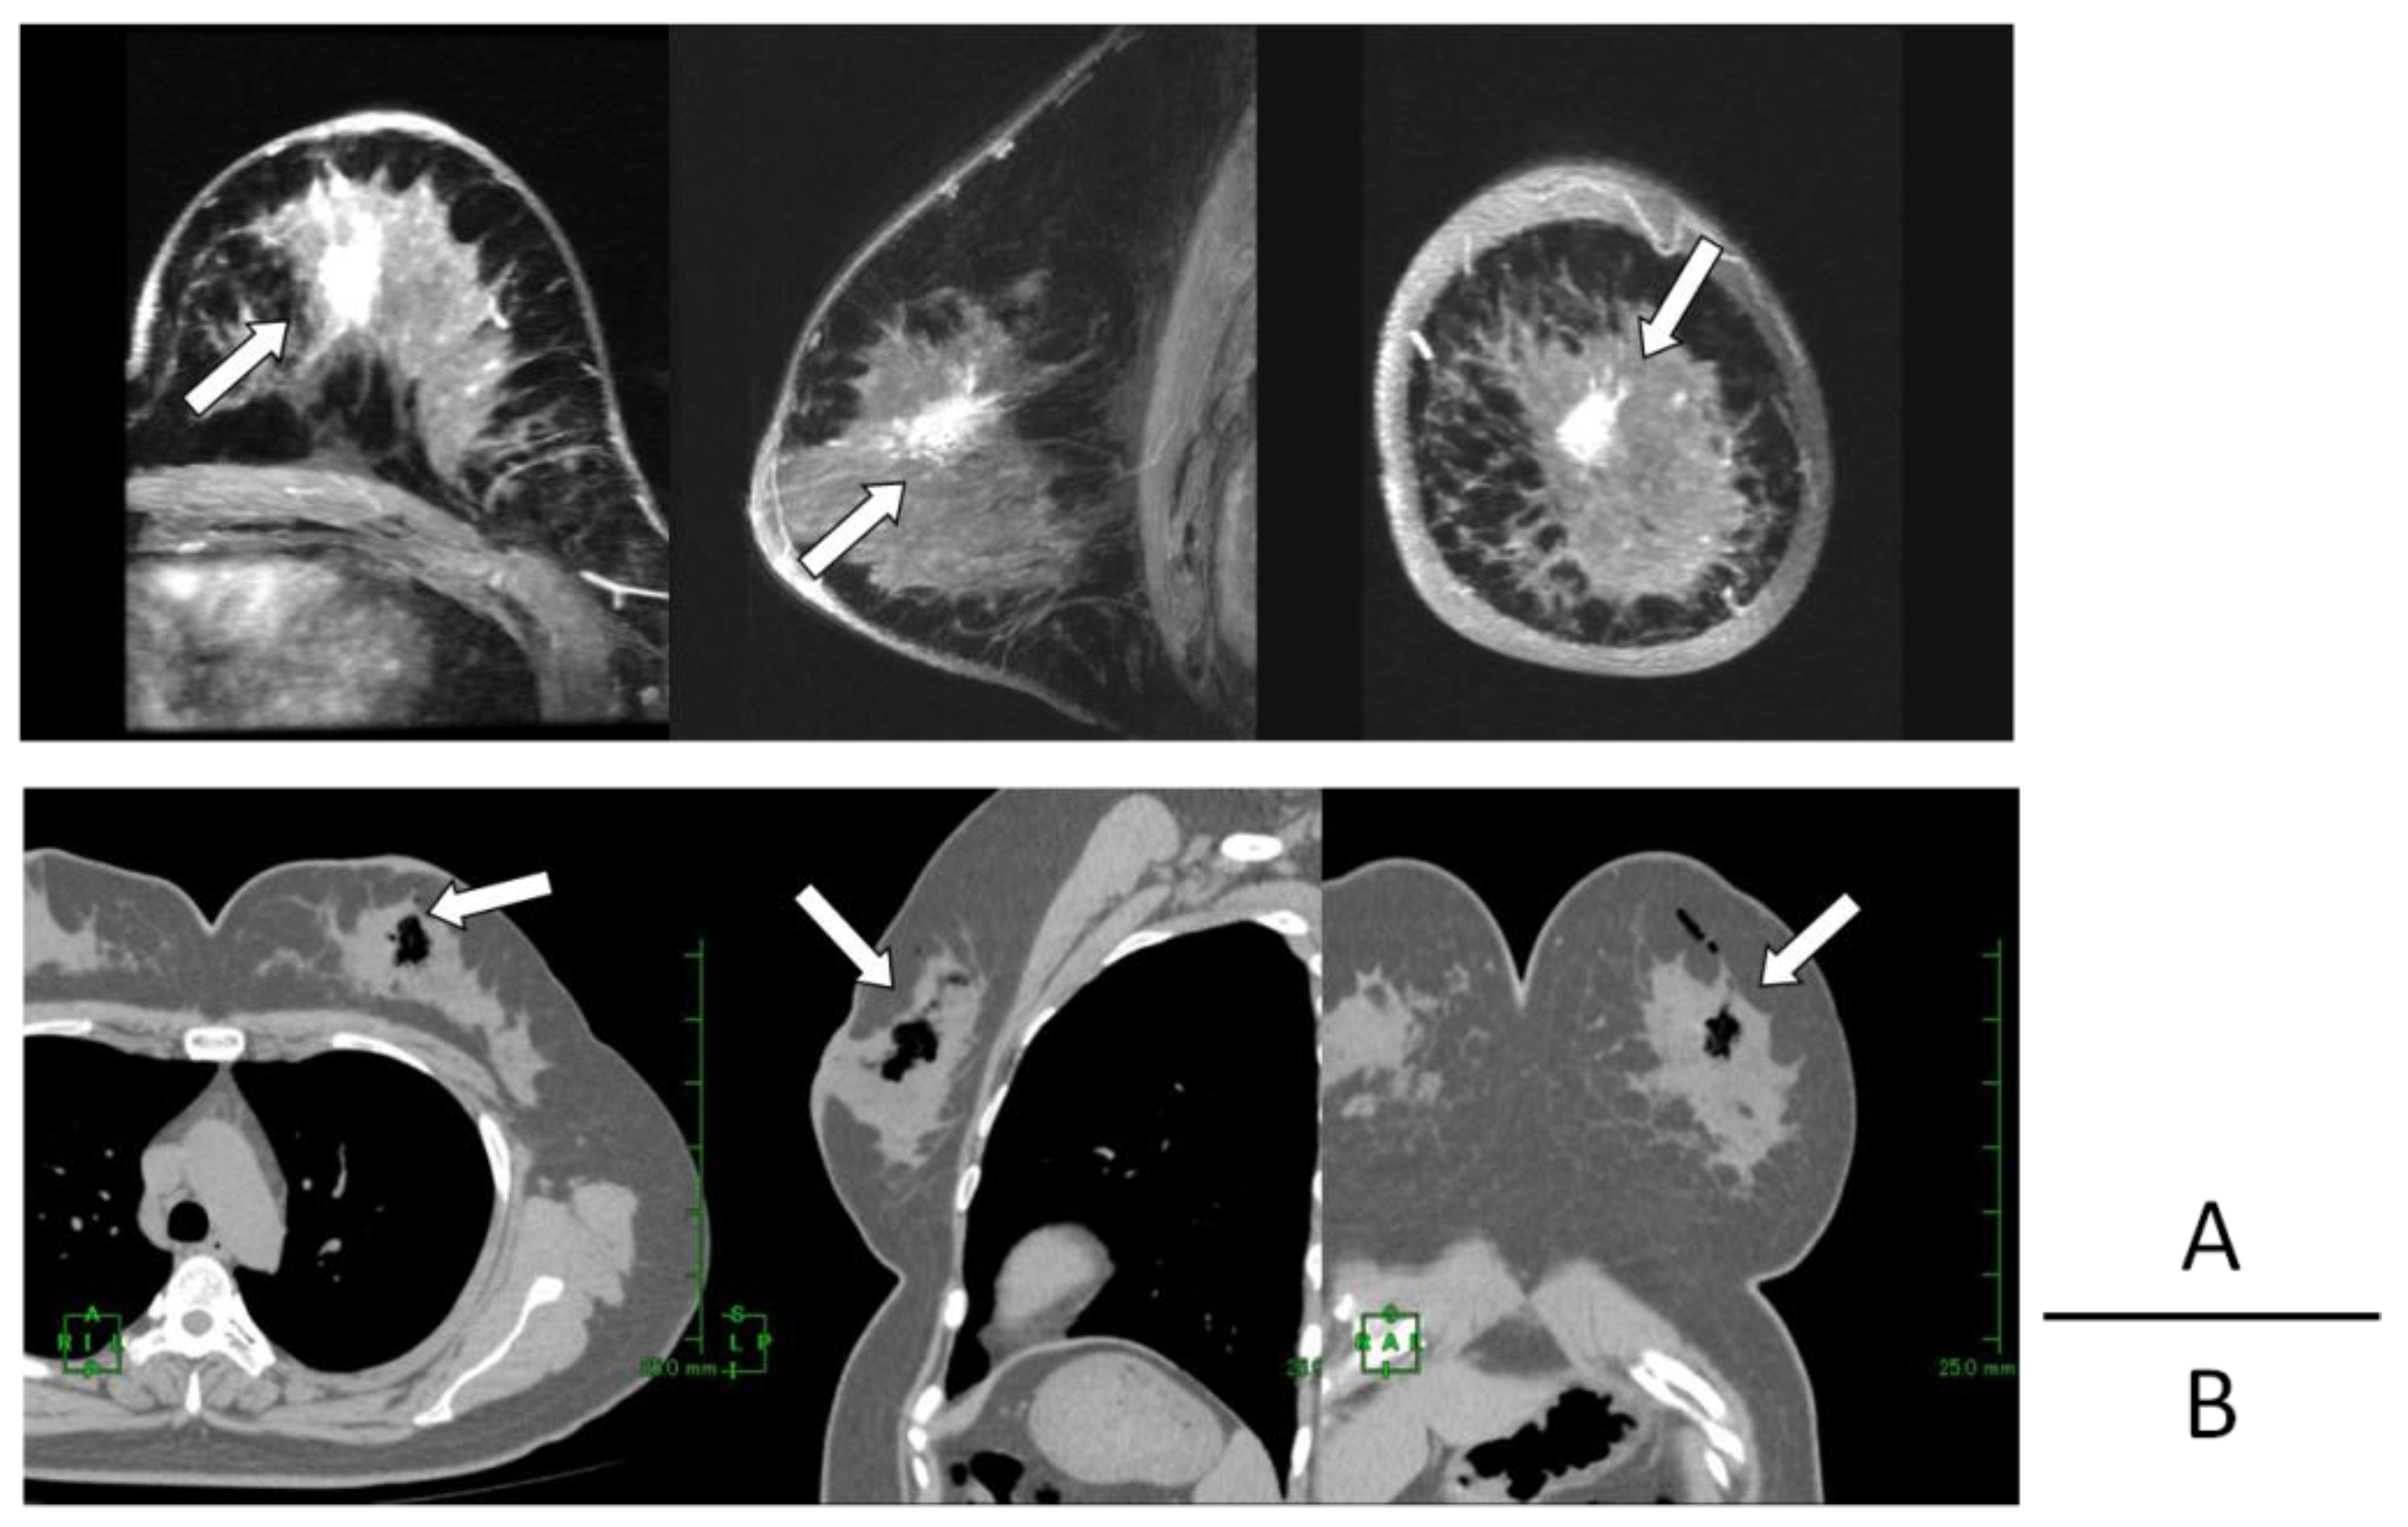

Computed Tomography Demonstration of the Production and Distribution of Oxygen Gas Following Intratumoral Injection of a New Radiosensitizer (KORTUC) for Patients with Breast Cancer—Is Intratumoral Injection Not an Ideal Approach to Solve the Major Problem of Tumor Hypoxia in Radiotherapy?

Hayashi, N.; Ogawa, Y.; Kubota, K.; Okino, K.; Akima, R.; Morita-Tokuhiro, S.; Tsuzuki, A.; Yaogawa, S.; Nishioka, A.; Miyamura, M. Computed Tomography Demonstration of the Production and Distribution of Oxygen Gas Following Intratumoral Injection of a New Radiosensitizer (KORTUC) for Patients with Breast Cancer—Is Intratumoral Injection Not an Ideal Approach to Solve the Major Problem of Tumor Hypoxia in Radiotherapy? Cancers 2016, 8, 43. https://doi.org/10.3390/cancers8040043